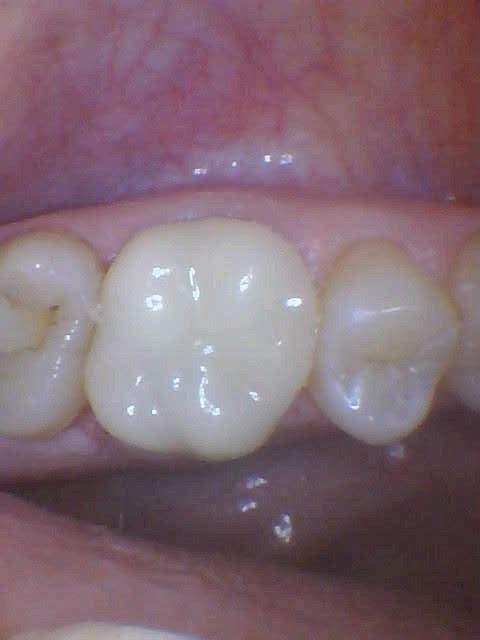

Cusp fractured off upper molar, fixed with same day crown.

Before

After